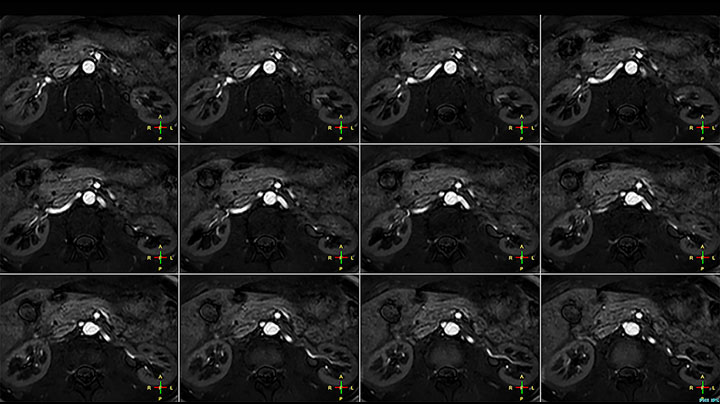

Although the area between the neck and the top of the lung is one of the most difficult areas for MRI, Prodiva 1.5T images show good quality in this 56-year-old male with Pancoast tumor on the right. mDIXON TFE images shows excellent fat suppression in the neck area and the DWI shows almost no distortion.

Acq voxel size 1.2 x 1.3 x 2.4 mm, Recon voxel size 0.7 x 0.7 x 1.2 mm, dS SENSE factor 2, scan time 5:46 min.